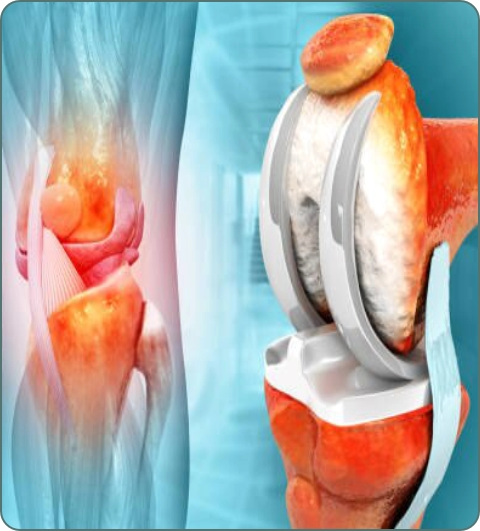

Total Joint Replacement

Hip, knee, and shoulder replacements using artificial joints. Restores mobility and relieves pain in severe arthritis cases.